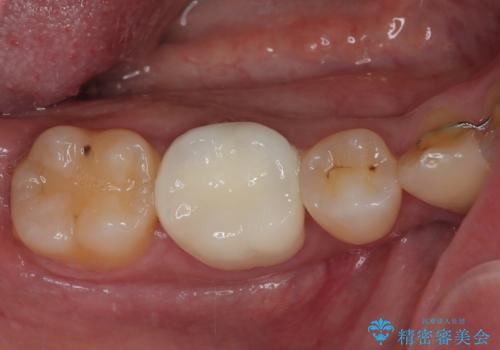

銀歯をセラミックにしたい オールセラミッククラウン

担当医 有澤哲郎